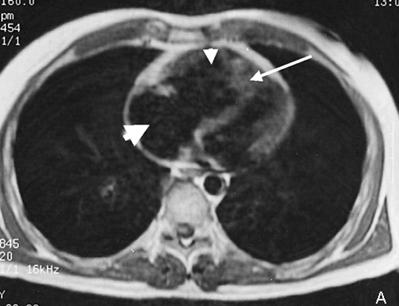

Ecocardiograma: marire a cavitatilor drepte (VD si AD), miscare paradoxala a septului interventricular (cu 'protruzie' a acestuia spre cavitatea VS mai ales in formele severe), regurgitare tricuspidiana cu jet de minimum 3,0 m/s la ex. Doppler, uneori regurgitare pulmonara (insuficienta pulmonara); in forme severe de HTP pot aparea semne de debit transmitral mic.

Imagine Rx. de profil cu HVD Aspect CT de HTP primara